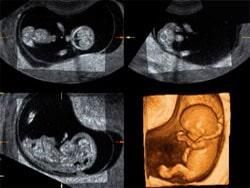

Como médico ginecóloga-obstetra, la Dra. Karla Patricia Palacios Ramírez se dedica a brindar consultas ginecológicas ante enfermedades de la mujer; da atención y seguimiento oportuno y puntual durante el embarazo a mujeres en Los Mochis, Sinaloa.

La ginecóloga se enfoca en dar atención a la salud femenina en todas las etapas, incluyendo la pediátrica, adolescencia, juventud, vida reproductiva, climaterio y menopausia.